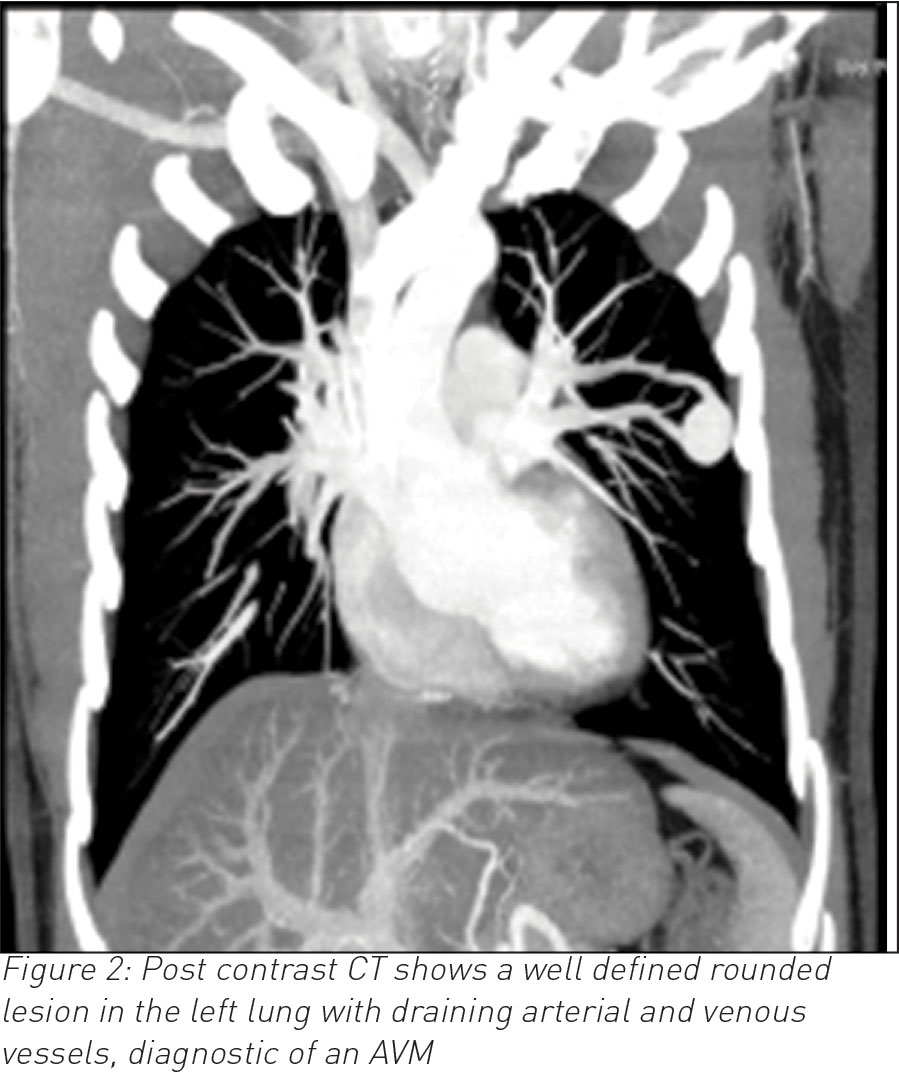

A 35-year-old male, who is otherwise fit and healthy, presented with a 10-day history of cough and temperature. Bloods showed raised white cell count otherwise normal. Chest infection was suspected and a chest radiograph was requested. The latter showed a well-rounded soft tissue opacity in the left midzone with possibly a connecting vessel radiating to the hilum. Two smaller opacities were identified in the right lung. A computed tomography (CT) pulmonary angiogram with intravenous contrast followed and that confirmed the diagnosis of a PAVM of 2cm in the left upper lobe and exquisitely demonstrated the feeding artery and vein with further smaller PVMs of 1cm in the right lung. The patient declined any further intervention.

CT is often the diagnostic modality of choice.3 It differentiates PAVMs from other causes of pulmonary nodules or masses. On CT, the characteristic presentation of a PAVM is a homogenous non-calcified nodule up to several centimetres in diameter or a serpiginous mass connected with blood vessels. Occasionally associated phleboliths may be seen as calcification. Contrast injection shows enhancement of the feeding artery, aneurysmal part and the draining vein.3